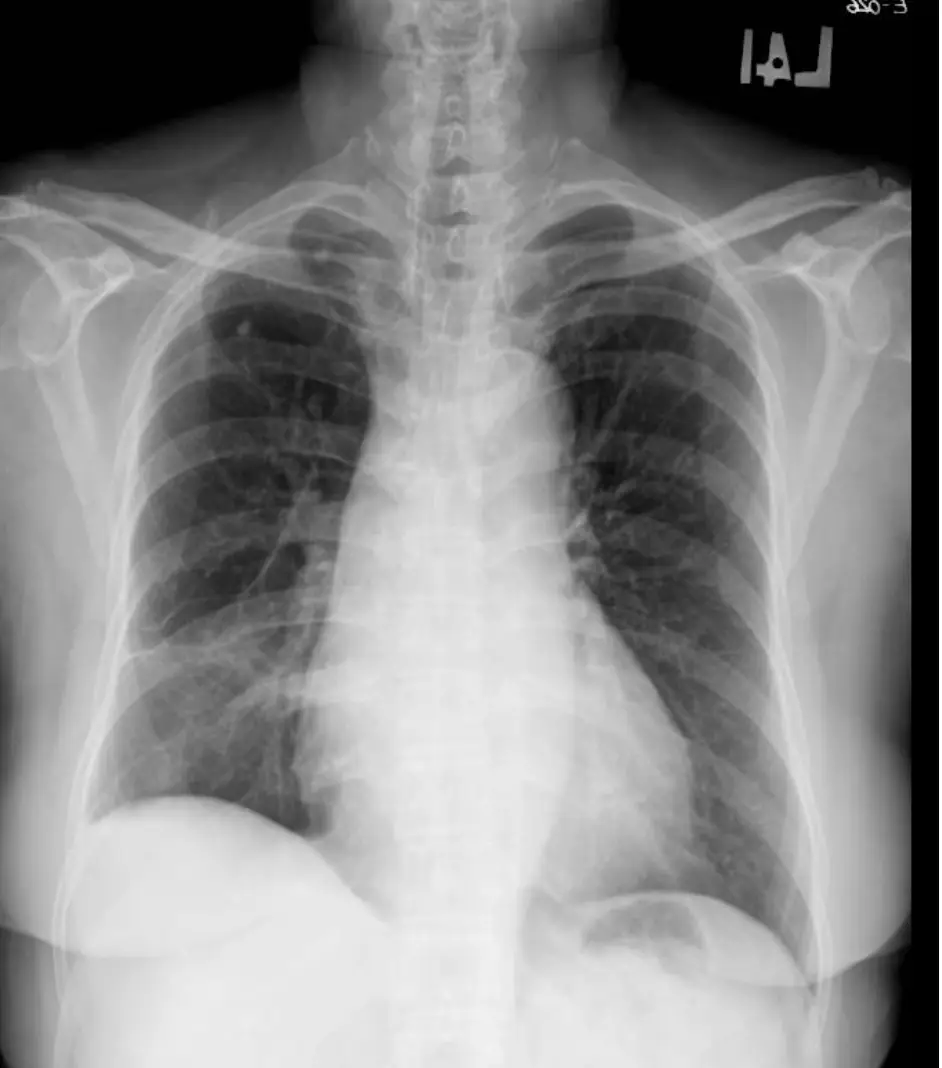

病人64歲家庭主婦,近三個月來有間歇性胸悶及運動性呼吸困難。病人有氣喘及高血壓10年病史,規則 服用Ipratropium或Furosemide + Aldactone + Digoxin + Aspirin。事實上病人過去10年前就有類似症 狀,再多加服用上列藥物,也就改善。只是近月來全身倦怠,食慾不振,上腹微痛及體重減輕七公斤,乃 於七月廿六日住院診療。病人Height: 156 cm Weight: 68kg ; T/P/R:37.1/88/16;。 BP: 110/73 mmHg。理學檢查發現心臟大小正常,規則律跳,唯心尖處(Apical area) 有雙峰脈波bifid pulse) 及在左上 胸緣及心尖處有Gr 4/6 Pansystolic murmur,下肢有2度浮腫,但其他器官並未有異常。血球檢 查:WBC,10.14k/uL; RBC, 4.79 M/uL; Platelet, 169K/uL。血液生化結果: Albumin, 4.2 gm/dL; T-Bil, 0.86 mg/dL; BUN, 16.8 mg/dL; Cre1.0 mg/dL; ALT, 90 U/L。其心電圖及胸部X光如圖。經心導管檢查: 大動脈 血壓, 142/68 mmHg; 左心室出口部( LVOT), 158/28 mmHg; 左心室心尖部, 198/32 mmHg. 其左心室造影 及Cardiac CT如圖。請問病人的正確心臟診斷是: 圖片描述 圖片描述 圖片描述 圖片描述

1. 胸部X光

心臟輪廓無明顯擴大,肺野無顯著充血或積液跡象,提示非擴張型心肌病或重度心衰主導(與擴大性心肌病、嚴重心衰不符)。